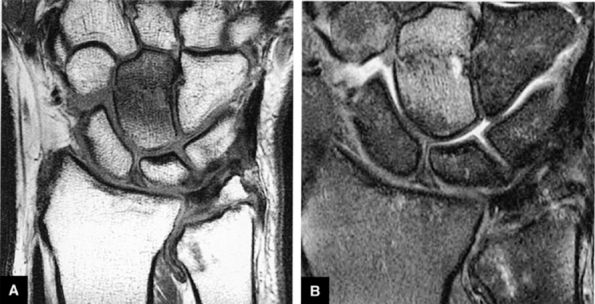

FIGURE 10.2 ● Optimized signal-to-noise in routine wrist imaging using a four-channel phased-array wrist coil on a 3T imager. (A) Coronal PD FSE image. (B) Coronal FS PD FSE image. (C) Axial PD FSE image.